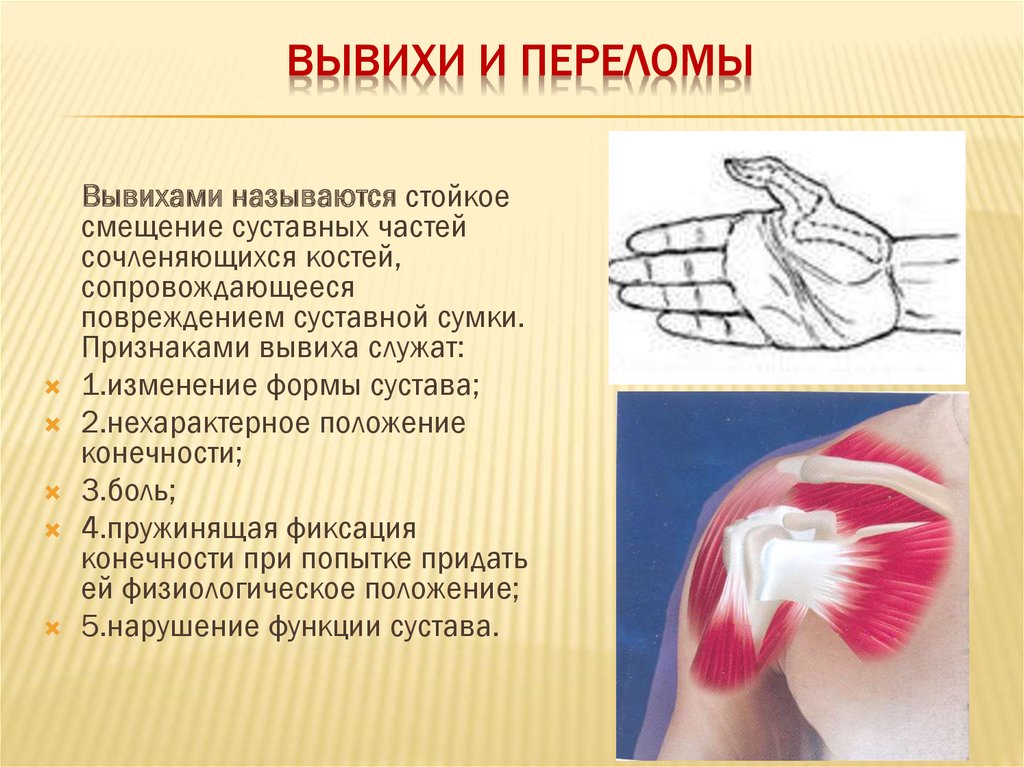

Вывихи и переломы ключицы презентация - 85 фото